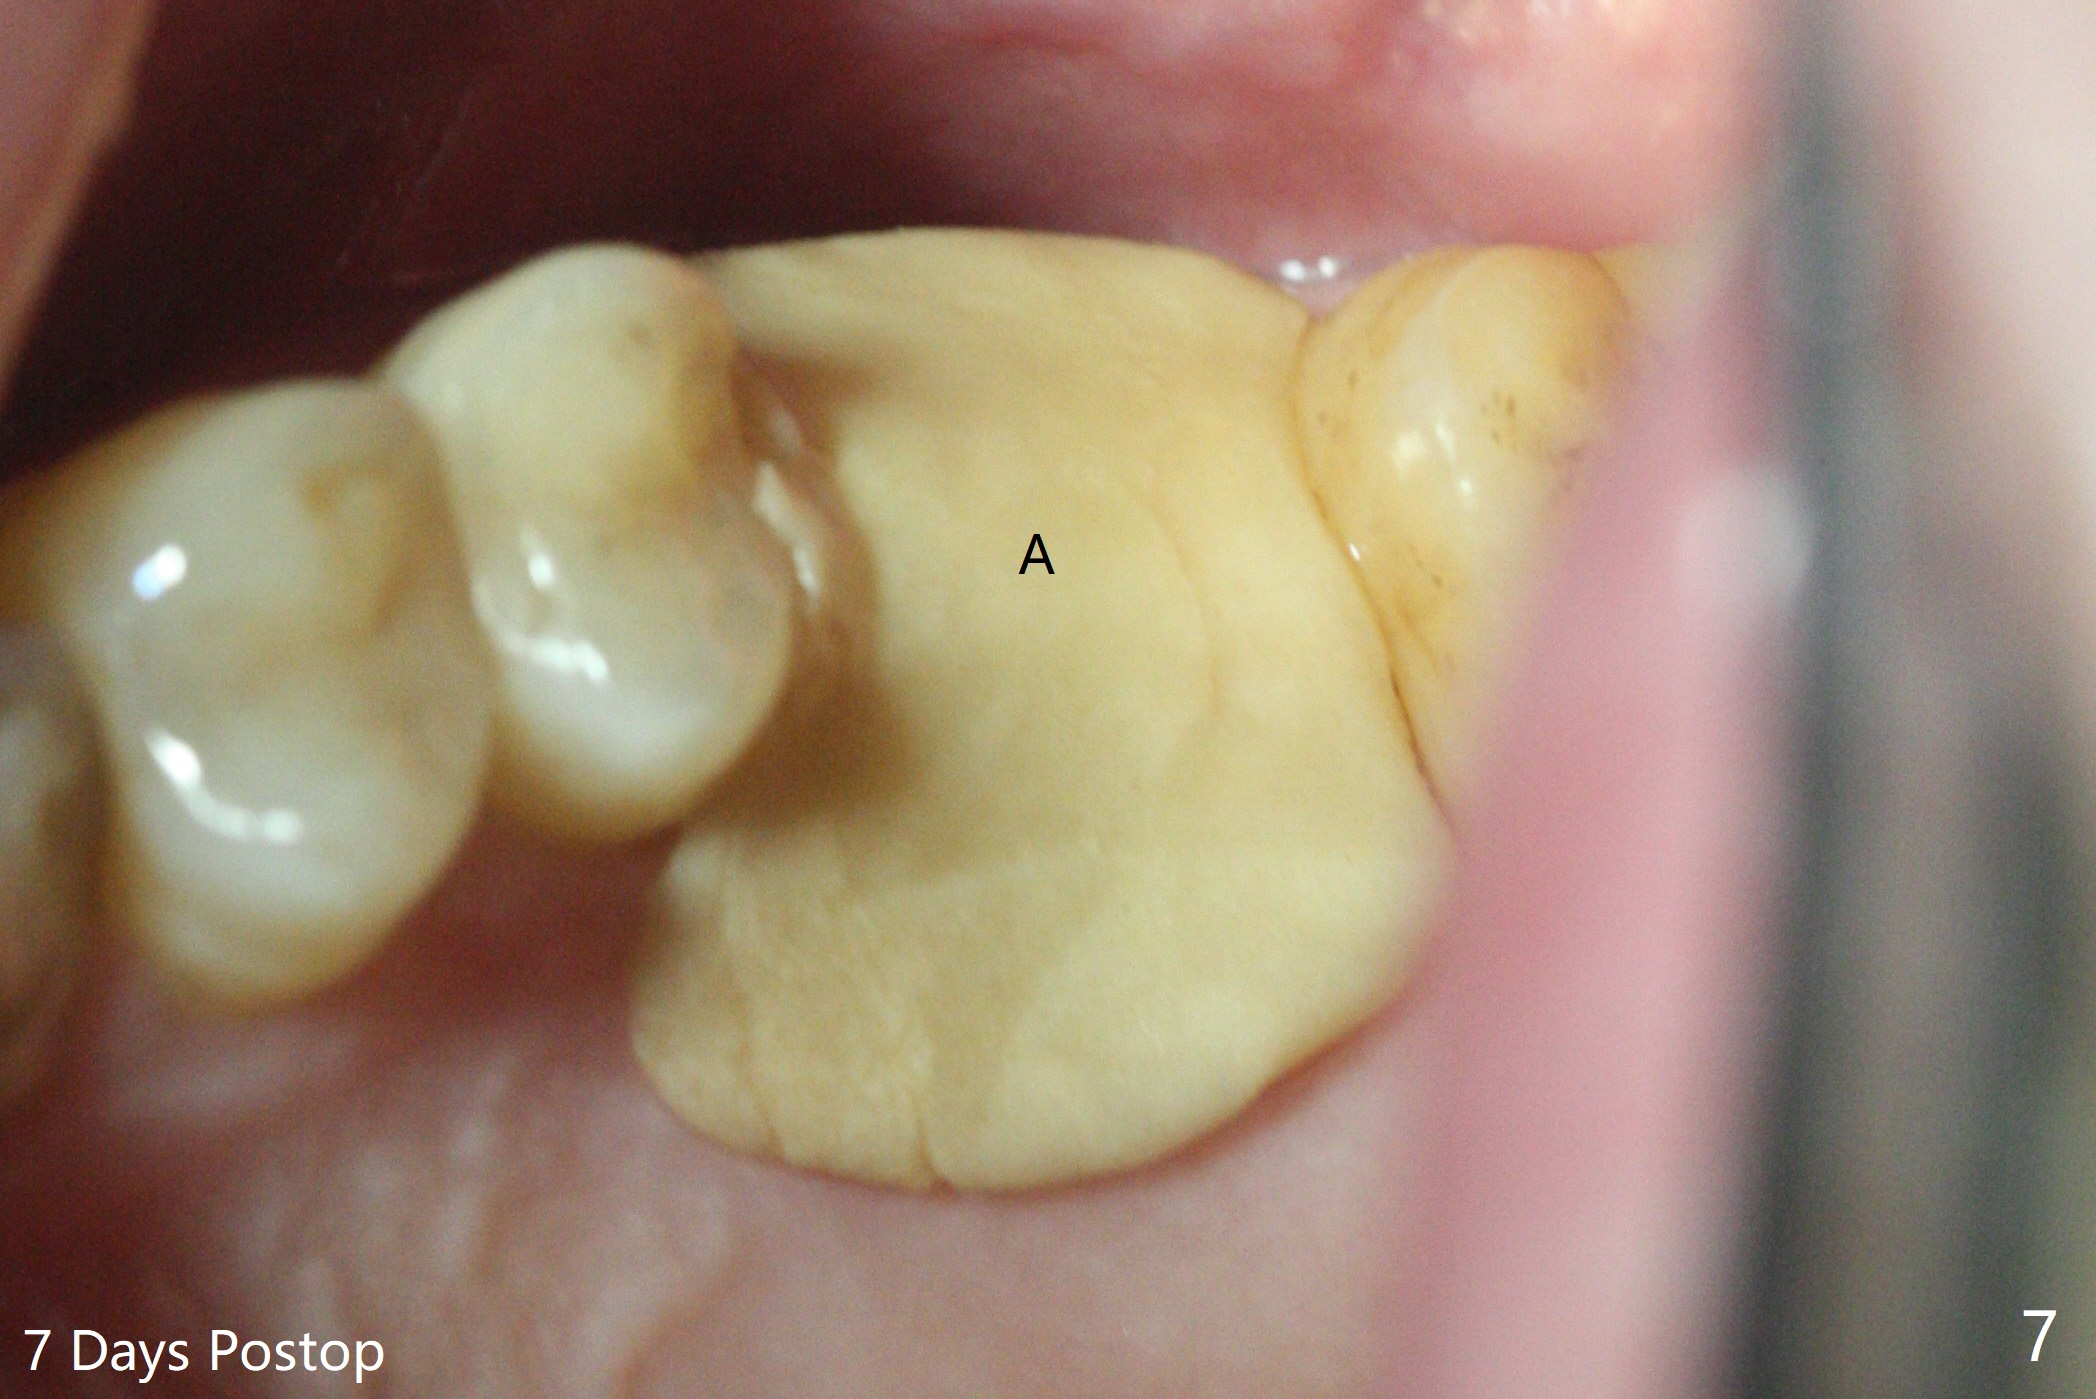

72岁男14号牙腭侧根尖接近上颌窦(图一,二:P),牙齿拔除后,根尖对刮治敏感,冲洗后,开始导板钻洞,圆钻穿透窦底,放置粘性骨粉和报废植体提升(图三:箭头)。放置小张PRF和骨粉(图四:箭头),植入正式植体,基台和骨粉(图五:*),最后覆盖PRF(图六),为了防止骨粉从邻牙牙龈沟(>)丢失,覆盖树脂敷料。基台和前后邻牙使树脂敷料术后一周巍然不动(图七:A)。术后一个月撤除树脂敷料,牙槽窝已经愈合(图八)。再过两周牙槽窝上皮好像进一步成熟(图九),然后塞入一个龈线,制备临时牙冠。